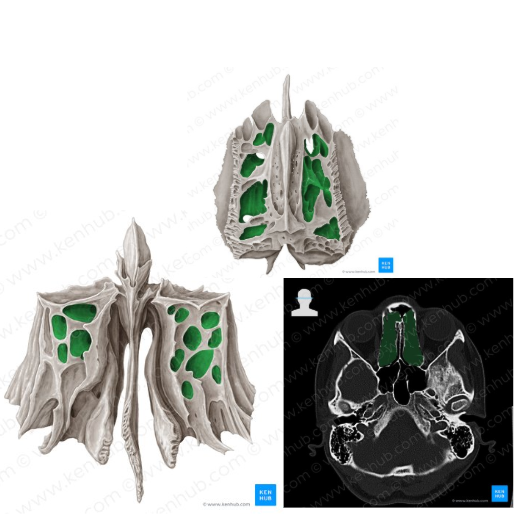

Celdillas etmoidales

Cavidades neumáticas. Dan volúmen con poca masa al cráneo.

Parte de los senos paranasales.

Laberintos Etmoidales

Contiene muchas cavidades neumáticas

Celdillas etmoidales, se dividen en anteriores y posteriores

Meato superior

Las celdas etmoidales POSTERIORES drenan a este meato

Meato medio

Las celdas etmoidales ANTERIORES, el seno frontal y el seno maxilar drenan a este meato